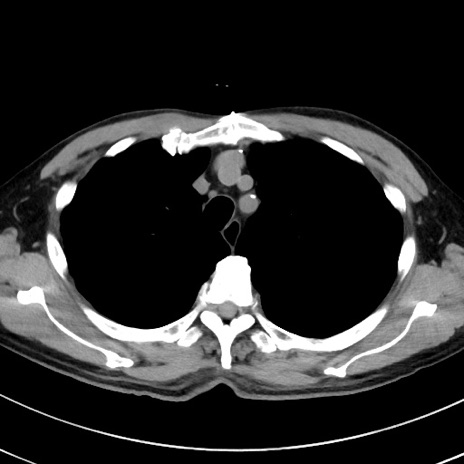

症例38(横断像)

【症例】70歳代 男性

【主訴】腹痛・嘔吐

【現病歴】昨晩より、嘔吐・腹痛あり。今朝になっても嘔吐あり。来院。

【既往歴】心臓バイパス手術、開腹胆摘、腸閉塞

【身体所見】BP 107/71mmHg、HR 116/min、腹部:平坦、軟、下腹部に軽度圧痛あり。反跳痛なし。

【データ】WBC 15100、CRP 0.32